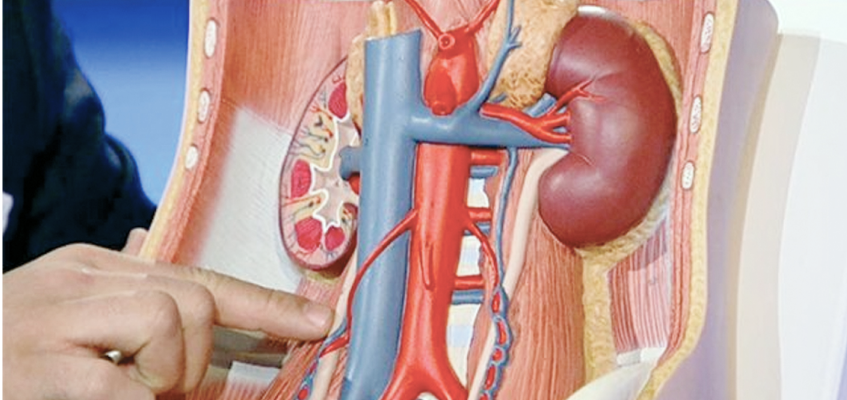

Что представляет собой киста почки? Это новообразование, имеющее объемную округлую форму. Как правило, доброкачественное. Развивается в различных структурах органа: на полюсах почки, в периферической части (корковое вещество), в системе накопления и выведения мочи. В большинстве случаев, содержит серозное наполнение.

-

по расположению: тканевыми (паренхиматозными), почечносинусными (ворота почки), интрапаренхиматозными (ткани почечной капсулы).